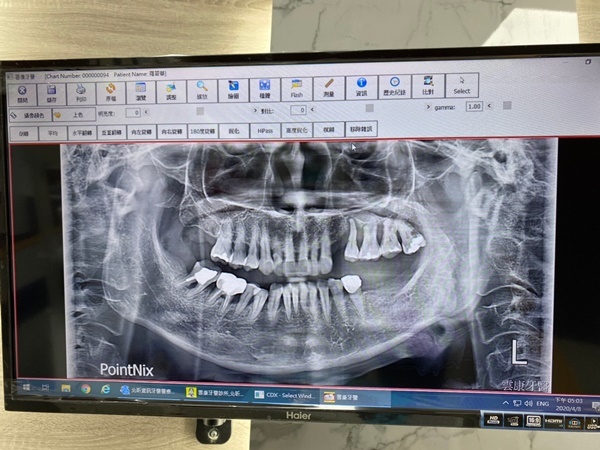

和植牙醫師一起看著剛剛拍出來的X光片

後面幾顆臼齒簡直慘不忍睹….

自以為只有一點點蛀牙誰曉得是牙裂到七零八落

有幾顆牙面蛀很深幾乎已跟牙齦面平鋪

x光片搭配斷層掃描片子來確認植牙手術精準度